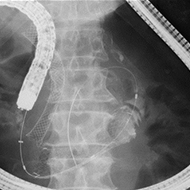

膵癌による十二指腸狭窄に対する十二指腸ステント+胆管ステント

十二指腸乳頭を切開(EST)あるいはバルーン拡張(EPBD)した後、総胆管や膵管内の結石を 除去します。

多数の総胆管結石が積み上げ状に存在する場合や巨大な総胆管結石の場合には、大口径 バルーン(EPLBD)での乳頭処置を行うことで、少ない処置回数、短時間での治療が可能です。

大口径バルーンによる乳頭拡張術